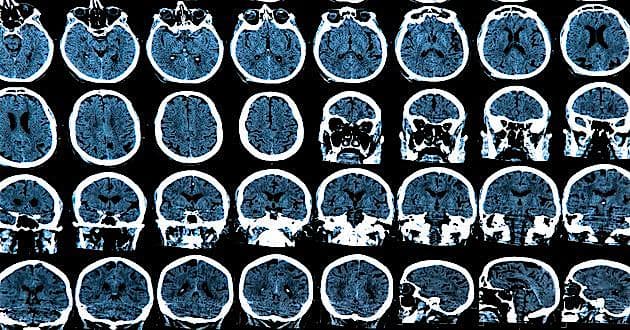

En genetisk variant, der beskytter mod Alzheimers sygdom, findes langt sjældnere i den danske befolkning end i de øvrige nordiske befolkninger, skriver Syddansk Universitet i en pressemeddelelse, som henviser til et nyt studie fra universitetet.

Genvarianten beskytter mod ophobning af proteinet beta-amyloid i hjernen, der er en væsentlig årsag til Alzheimer og resulterer i svigtende hjernefunktion og demens, fremgår det.